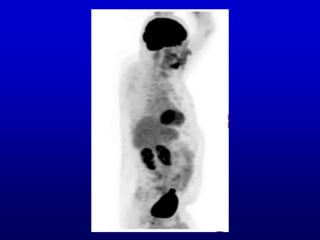

Next I will show you a rotating 3D

display called a MIP, from a 3D

bone scan of a patient with a lesion

in one sacroiliac joint (among a

number of abnormalities). Then I

will ask you whether it is the right or

left sacroiliac joint. I would not

strain your brain about this, just

form an impression without

enduring great anxiety over

whether it is correct or not.

Next I willshow you a rotating 3D display called a MIP, from a 3D bone scan of a patient with a lesion in one sacroiliac joint (among a number of abnormalities). Then I will ask you whether it is the right or left sacroiliac joint. I would not strain your brain about this, just form an impression without enduring great anxiety over whether it is correct or not.

• #7 You should get a sense of 3D, which is the point, and you should see that one of the sacroiliac joints has a much more intense signal (that is, darker) than the other. Is it the left of the right?